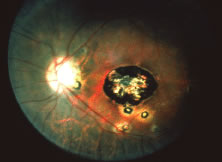

A variable number of eyes, up to 75%, develop retinal detachments (Fig. 5). Prophylactic laser for demarcating the areas of active retinitis from normal retina has been advocated to create chorioretinal adhesions that prevent retinal detachments around sites of retinal break formation (which usually occur at the zone between affected and healthy retina). Han and associates43 reported five cases treated with prophylactic laserpexy in addition to antiviral, steroid, and antiplatelet therapy. After 15 months of follow-up, no retinal detachments were noted. Sternberg and coworkers44 described a 75% decrease in the rate of retinal detachment using prophylactic photocoagulation. Some have advocated the creation of a “new ora serrata” by applying confluent rows of laser burns posterior to the areas of retinitis. However, if traction forces from vitreous organization, epiretinal membrane (ERM) formation, or proliferative vitreoretinopathy develop as they commonly do, the contractile forces will be able to overcome any increased chorioretinal adhesion created by the laserpexy. However, McDonald and associates45 reported failure of prophylactic peripheral laserpexy to prevent retinal detachment in ARN patients. In addition, many cases of ARN result in a severe vitritis, limiting the view for a planned laserpexy (Fig. 6). Therefore, vitrectomy with endolaser and concomitant encircling of the eye with a scleral buckle to reduce traction may be required in some patients.46,47 Decisions relating to the need for scleral buckling to support retinal breaks and the use of silicone oil or long-acting gases to repair retinal detachments should be made by an experienced vitreoretinal surgeon.40,48 Selection of cases to undergo operation should be made with consideration given to optic nerve function, visual potential, and medical control of retinitis.

Fig. 5. A patient with funnel-shaped retinal detachment and proliferative vitreoretinopathy complicating acute retinal necrosis syndrome.